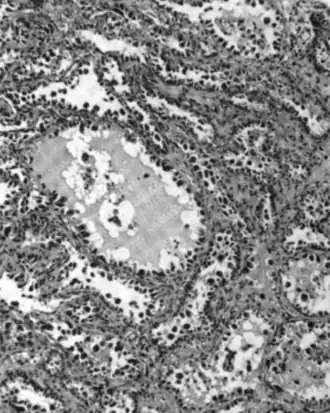

| Micrograph of a mucinous ovarian carcinoma stained by H&E | |

Mucinous tumors include mucinous adenocarcinoma and mucinous cystadenocarcinoma.[29]

Mucinous adenocarcinoma

Mucinous adenocarcinomas make up 5–10% of epithelial ovarian cancers. Histologically, they are similar to intestinal or cervical adenocarcinomas and are often actually metastases of appendiceal or colon cancers. Advanced mucinous adenocarcinomas have a poor prognosis, generally worse than serous tumors, and are often resistant to platinum chemotherapy, though they are rare.[29]